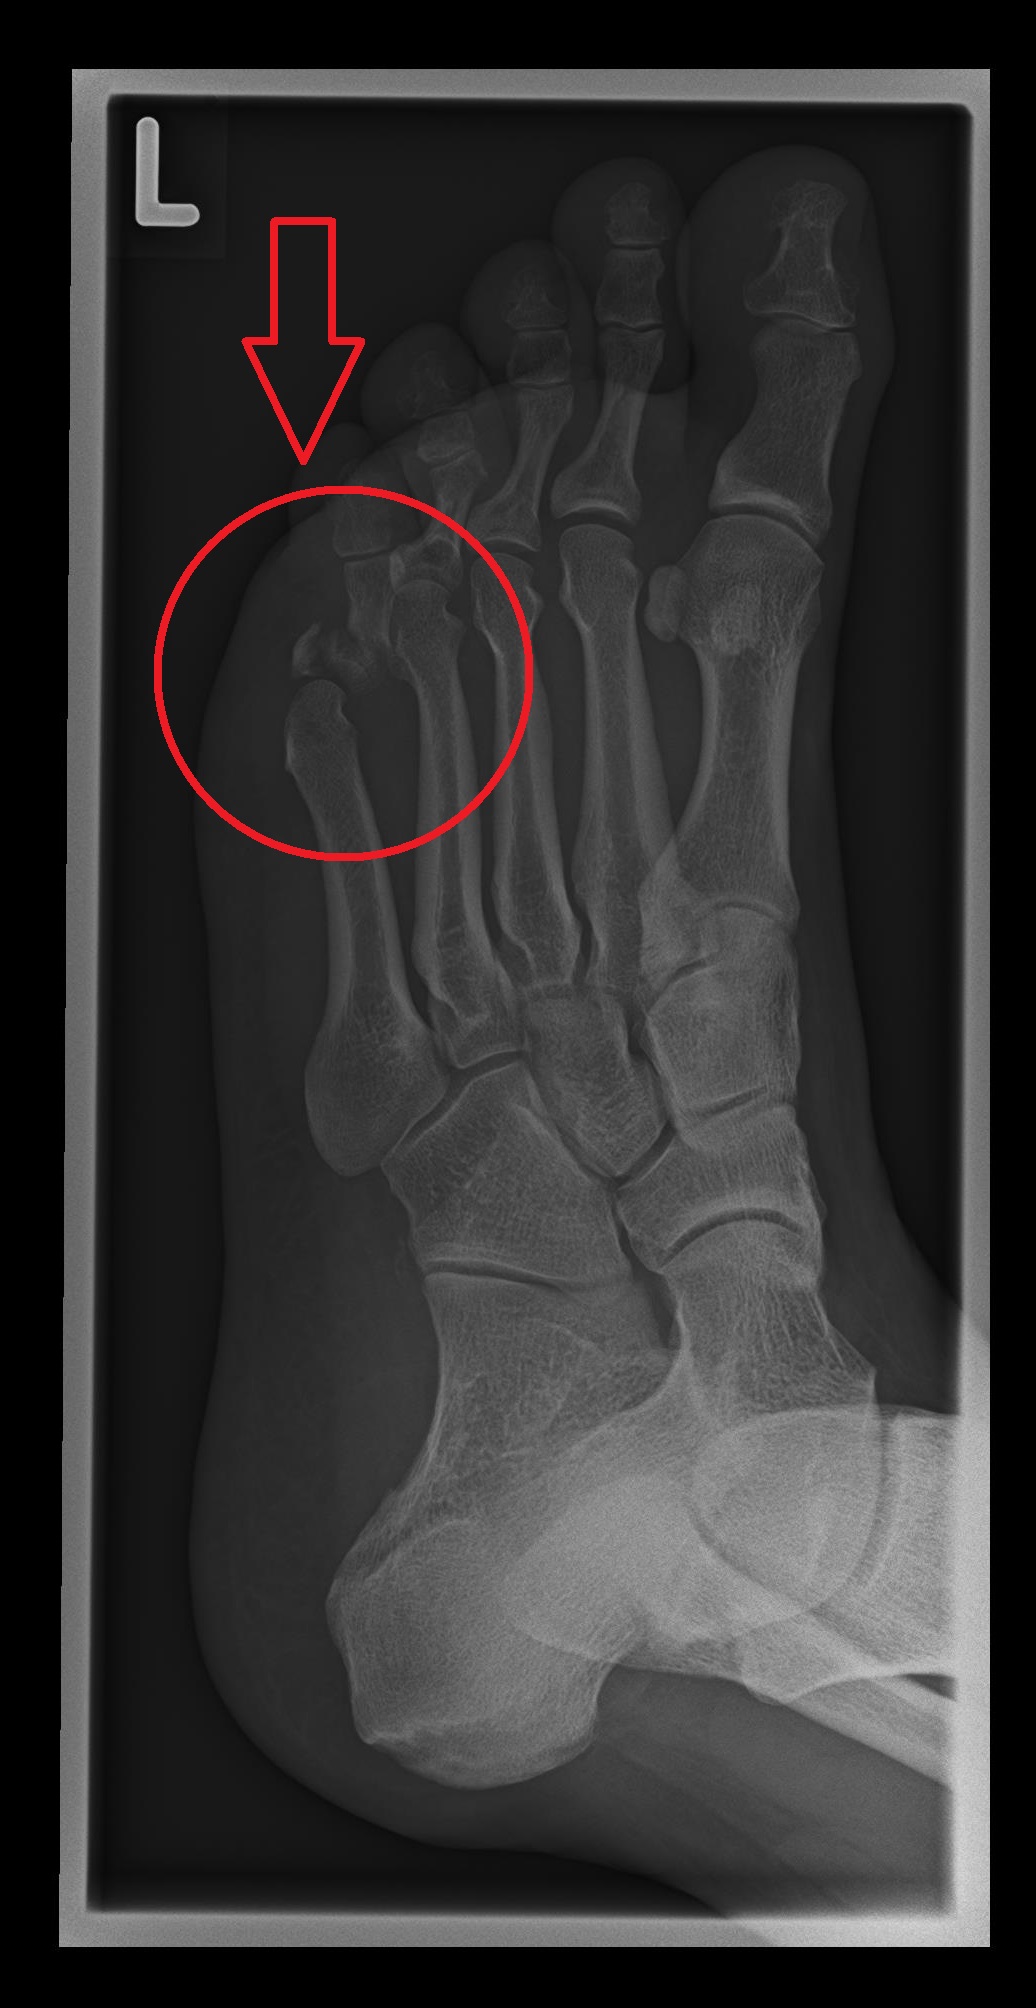

Der gebrochene Zeh infolge des Unfalls

Bild in Originalgröße 283 KB | Bild anzeigen Anzeigen Bild herunterladen Download